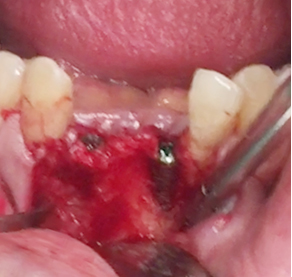

Simultaenous bone grafting for implants

Simultaneous bone graft and implant placement